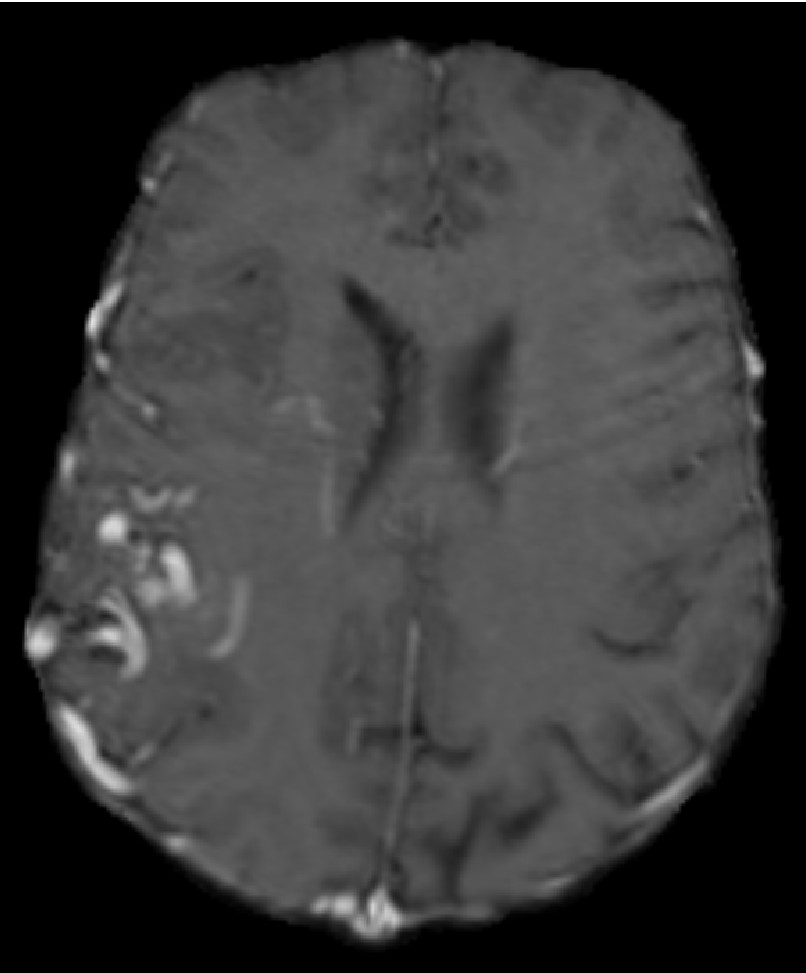

Figure 1: Brain MRI slice with AVM after skull stripping [5] LABEL:sub@DoeOne and after segmentation LABEL:sub@DoeTwo. LABEL:sub@DoeThree depicts a volume rendering of the segmented AVM. The segmented image has a spacing of 0.7×0.7×1.6mm30.70.71.6superscriptmm30.7\times 0.7\times 1.6\;\text{mm}^{3}0.7 × 0.7 × 1.6 mm start_POSTSUPERSCRIPT 3 end_POSTSUPERSCRIPT and a size of 320×320×100voxels3320320100superscriptvoxels3320\times 320\times 100\;\text{voxels}^{3}320 × 320 × 100 voxels start_POSTSUPERSCRIPT 3 end_POSTSUPERSCRIPT.

The previous work [11, 12, 5] re-samples the segmented image to an isotropic unit-spaced image to avoid the transformation of the index to physical coordinates and vice versa. This approach is sufficient for fairly regular geometries and improves the speed of the mesh generation. However, in the case of complex data (i.e., AVM), image down-sampling can deteriorate the quality of the segmentation and may result in disconnected image regions or non-manifold connectivity (voxels that are connected to each other via an edge or a vertex). Figure 3 illustrates such an example. The presented method does not perform image down-sampling.

Refer to caption

(a) Before down-sampling (spacing: 0.879×0.879×0.879mm30.8790.8790.879superscriptmm30.879\times 0.879\times 0.879\;\text{mm}^{3}0.879 × 0.879 × 0.879 mm start_POSTSUPERSCRIPT 3 end_POSTSUPERSCRIPT)

(b) After down-sampling (spacing: 1×1×1mm3111superscriptmm31\times 1\times 1\;\text{mm}^{3}1 × 1 × 1 mm start_POSTSUPERSCRIPT 3 end_POSTSUPERSCRIPT)

Figure 3: Brain Arteriovenous Malformation (AVM) segmentation, before and after down-sampling. The red circles indicate the problematic regions after down-sampling (i.e., disconnected voxels or non-manifold voxel connectivity).